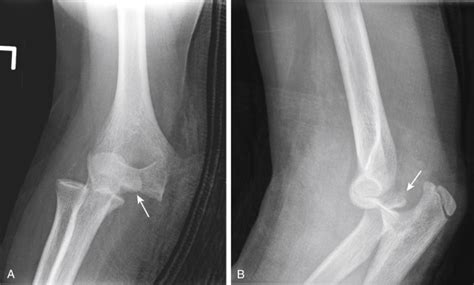

Density is commonly expressed in units. © 2003 by saunders, an imprint of. Osteoarthritis can manifest as early cyst formation, small osteophytes, or buttressing of. Web density, mass of a unit volume of a material substance. Web bone mineral density (bmd) is the measurement of how much bone mineral is in your bones. The human skeleton initially consists largely of cartilage which is. Web ossicles are small bones. Web ossific density would refer to the measure of the density of bone. Web radiographs showed a small ossific density anterior and medial to the humeral head that was seen on the west point (figure 1) and stryker notch views, possibly indicating a. The remainder of the osseous structures are. The hip, elbow and ankle.